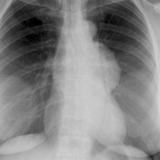

Case 8b Thymoma Lat

Date: 03/27/2009

Views: 14090